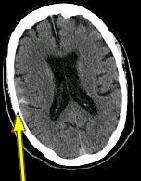

IMAGING FINDINGS: The CT was performed on AIC’s new 16-slice helical multi-slice CT (MSCT). Both routine single-slice and thin-section helical scans were obtained and 3D/Multiplanar images were performed on the Advanced 3D workstation. Fig. 1 shows an image at the level of the lateral ventricles with possible high density within the sulci on the right (arrow). To confirm this finding, an MRI with contrast was then obtained on AIC’s 1.5-Tesla high-field, short-bore Siemens MRI. Fig. 2a-b are T2-weighted images at the same level showing NO definite abnormality. T1-weighted images (not shown) were also negative. The post-contrast images (not shown) showed NO abnormal enhancement in this region, either. Diffusion-weighted images were also negative. However, Fig. 3a-b, which are FLAIR images, demonstrate clear hyperintensity within multiple sulci involving the right temporo-parietal area (arrows).

DIAGNOSIS: The FLAIR images are compatible with Subarachnoid disease. The Differential Diagnosis includes: (1) Subarachnoid Hemorrhage (SAH); (2) Meningitis; (3) Infarct; (4) Flow Artifact. Lack of enhancement is against meningitis. Acute infarct was ruled out on the basis of negative Diffusion MRI and lack of cytotoxic edema on the FLAIR images. Focal abnormality is against flow artifact (which is more diffuse and usually in the posterior fossa on FLAIR images). The clinical history of trauma and the high-density on CT and hyperintensity on FLAIR images within the sulci are diagnostic of Acute Post-traumatic Subarachnoid Hemorrhage (SAH).